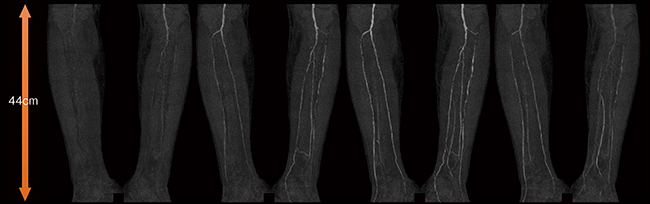

安齋副院長は,SOMATOM X.citeの有用性について広範囲4D撮影が実現した点を評価している。同院で行う血管内治療(EVT)の約半数は重症下肢虚血(CLI)で,1日あたり約2件の下肢4D撮影を行っている。また,大動脈ステントグラフト挿入術のエンドリーク評価に際しては,ステント上部の血管や側副血行路まで見えることが重要となる。観察範囲を4Dで評価するにはエリアディテクタCTでもカバーできないため,最大44cmの撮影範囲で4D撮影が可能なSOMATOM X.citeを導入した。これにより,術前の診断から術後のフォローアップまで有用な情報を得られるようになったという。

両下肢重症下肢虚血(CLI)に対する血管内治療(EVT)の1か月後フォローアップ検査画像。両下肢ともに治療後閉塞なく血流が保たれていることが確認できる。CLI患者のように左右の下肢で血流速度が違う場合,通常のCTAでは撮影タイミングの違いで血管抽出不良が生じる可能性があるため,4D撮影によって血流状態を把握することが重要となる(撮影範囲44cm,管電圧70kVp)。